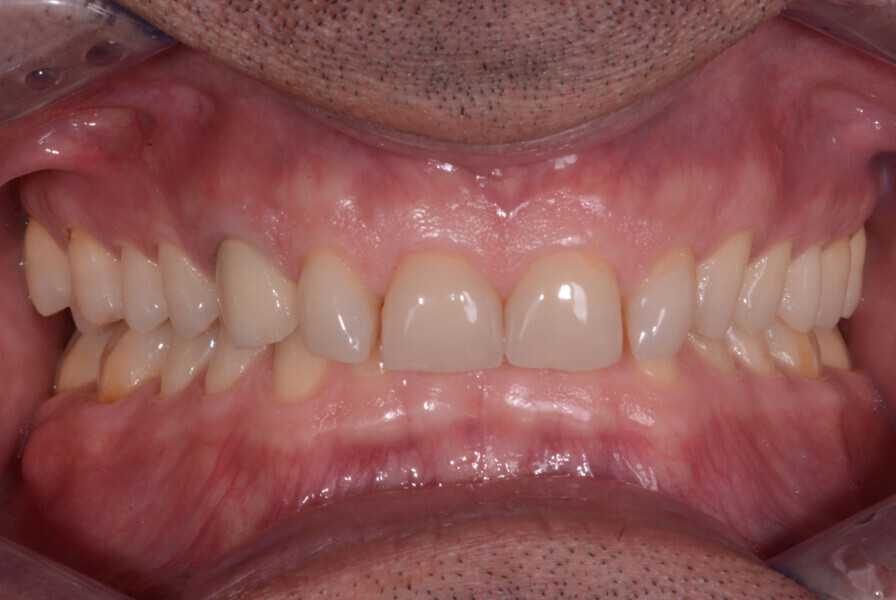

Fig. 5: DSD protocol: image of patient smiling wearing a lip and cheek retractor.